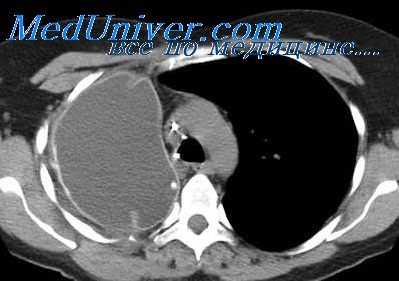

При полипозиционной рентгенографии грудной клетки в типичных случаях определяется шаровидная или овальная гомогенная тень средней интенсивности, с четкими контурами. При наложении тени средостения на тень кисты дополнительно требуется проведение пневмомедиастинографии или рентгенографии пищевода с бариевой взвесью. Установить анатомические взаимоотношения бронхогенной кисты с трахеобронхиальным деревом позволяет бронхоскопия и бронхография. При наличии признаков сдавления верхней полой вены или грудного лимфатического протока целесообразно выполнение флебографии и лимфографии.

Отличительным признаком тонкостенных бронхогенных кист служит изменение их конфигурации и положения при введении газа в средостение или плевральную полость (в отличие от дермоидных кист с толстой стенкой или плотных опухолей средостения). МСКТ грудной клетки в ряде случаев позволяет отказаться от проведения инвазивной диагностики бронхогенных кист и заранее спланировать объем вмешательства, поскольку дает исчерпывающую информацию о локализации и размерах образования.